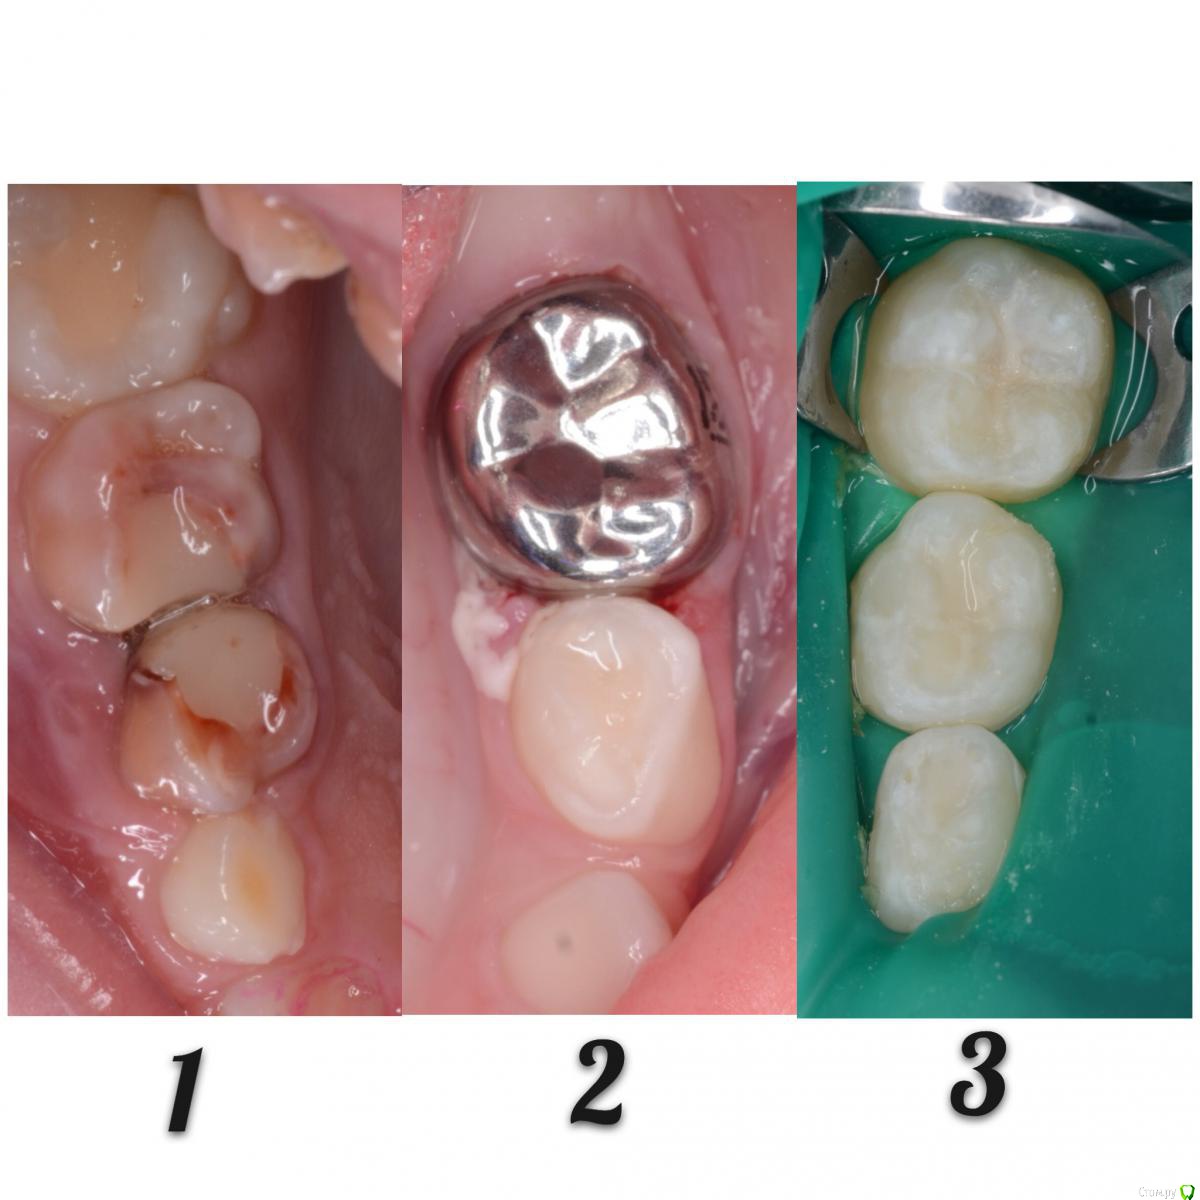

CRAZYDUCK Опубликовано 30 мая, 2018 Автор Поделиться Опубликовано 30 мая, 2018 Про обратимый пульпит .( ампутацию) Лечение методом витальной АМПУТАЦИИ. Даше в июле 6 лет . Познакомились мы полтора года назад , но сотрудничать не получилось , направлены для лечения в условиях общего обезболивания ( наркоз ) к ☺ @toothfairymila После лечения в условиях наркоза дети легче идут на контакт . Ребёнка не узнать - если до лечения в наркозе Даша даже в кресло садилась со слезами , то после - милые подарки , осторожно , но готова сотрудничать . Даша внимательно смотрит на моих ассистентов , взгляд изучающий ( можно этому человеку доверять или нет ). Маме Даши огромное спасибо - очень ответственно относится к регулярным осмотрам . Выявили скрытые кариозные полости и Даша доверилась лечиться в обычных условиях ( без наркоза ). 6.4 - обратимый пульпит , изначально было обширное разрушение , восстановлено пломбой в наркозе , поэтому лепить там пломбу ещё больше нет смысла. После ампутации -спонтанный гемостаз ( сравните с предыдущим случаем). Промываем ХГ 2% , мта на устья , IRM , коронка. 6.5 - обширная реставрация окклюзионно и начался кариес на медиальной контактной поверхности . Зуб должен меняться примерно в 10 лет ( 9-11 лет средний срок), то есть хочется , чтобы он постоял ещё года четыре , поэтому покрываем коронкой . Ждём Дашу на осмотр через 3-4 месяца.П.С. На заметку молодым коллегам - На снимке обвела зелёным нерентгенконтрастную реставрацию на зубе 6.3 , похоже на кариес , но это очень хорошая реставрация ! 1 Ссылка на комментарий

CRAZYDUCK Опубликовано 30 мая, 2018 Автор Поделиться Опубликовано 30 мая, 2018 Продолжительность лечения двух зубов меньше часа . 4 Ссылка на комментарий